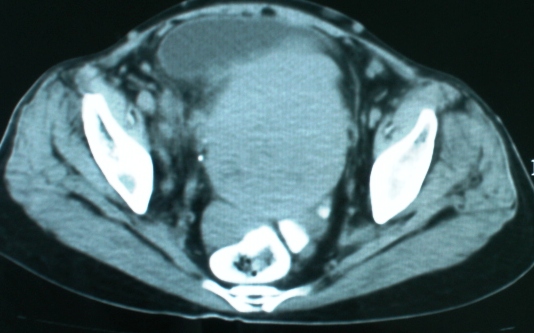

以下是引用zsl6918在2008-11-4 19:14:00的发言:[br]多发转移性改变,子宫改变不除外为原发灶